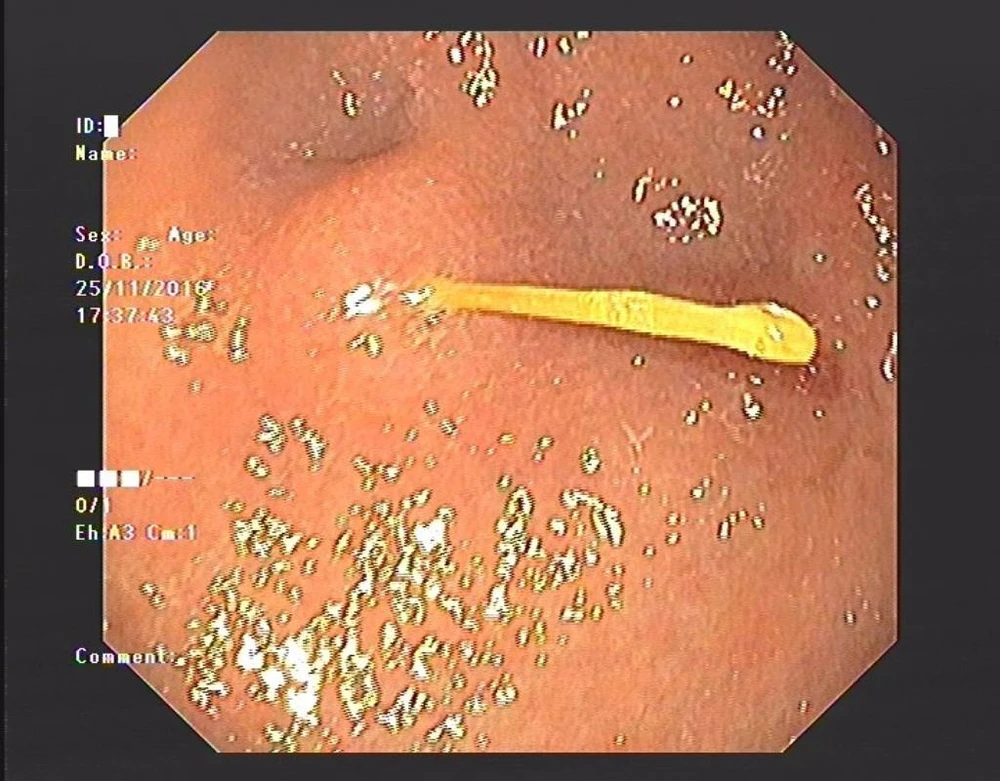

Cây tăm tre nằm trên thành dạ dày bà H.

Ngày 26-11, bệnh nhân PTH (45 tuổi, trú tại Nam Từ Liêm, Hà Nội), được người nhà đưa vào BV E (Hà Nội) cấp cứu trong tình trạng đau vùng thượng vị dữ dội. Khi nội soi, các bác sĩ phát hiện có vật nhọn nằm ở hang vị dạ dày. Sau khi gắp dị vật ra, thì đó là một cây tăm tre xỉa răng.

ThS-BS Lê Thị Ngọc, khoa Khám bệnh BV E, cho hay rất may cây tăm còn nằm ở thành trên dạ dày, đoạn này khá dày nên cây tăm chỉ làm xung huyết, gây loét hang vị và bị trầy xước nhiều vết từ thực quản đến dạ dày... Nếu không lấy ra kịp thời sẽ gây hoại tử thành dạ dày và nguy cơ thủng dạ dày rất cao.